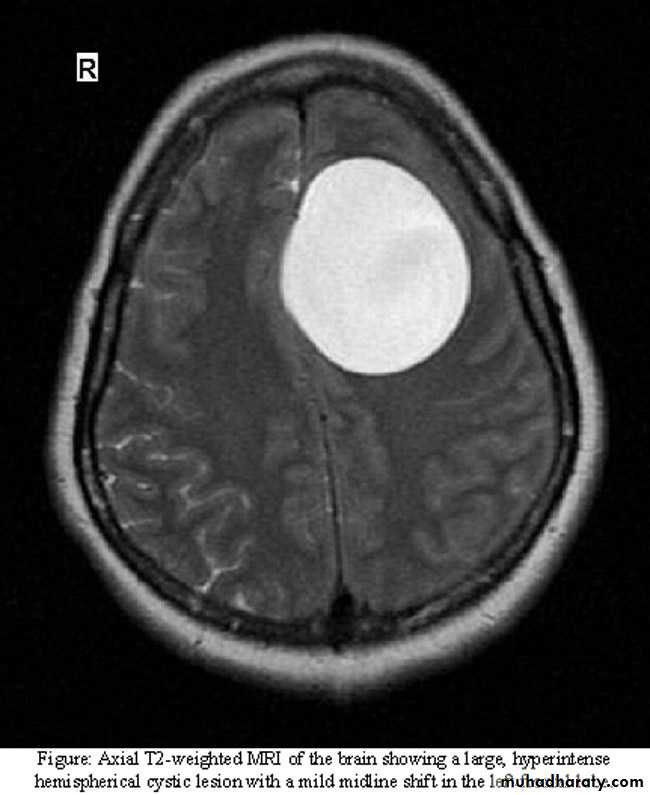

Brain MRI show. LF frontal lobe H.cyst